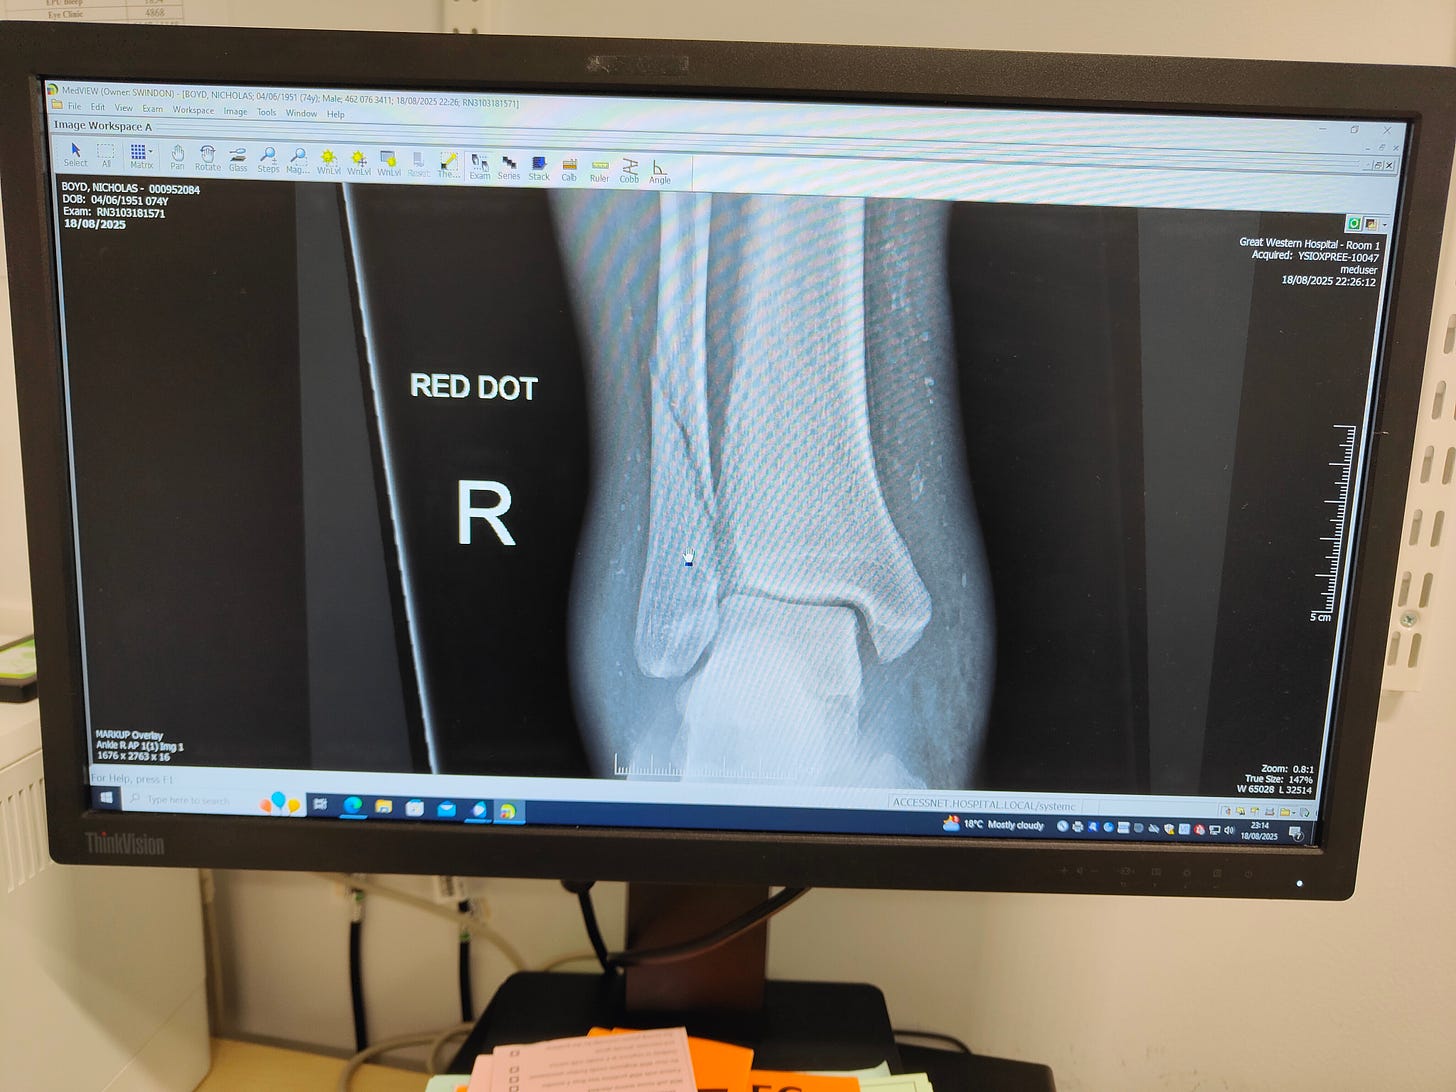

By 23:50, it was confirmed that I had broken my ankle; that I would be off everything for three weeks; that I would be wearing a Black Boot; that I was to avoid becoming a clot, by taking huge dollops of blood thinners and painkillers were great, but avoid Ibuprofen, because it hates blood thinners.